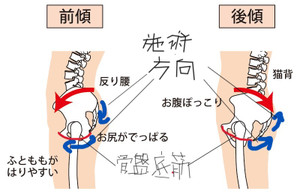

施術は、

尾骨からの骨盤底筋の操作と腸腰筋膜操作で行う尾骨からの施術です。

深くなり過ぎている場合(深腰)は浅く、浅くなり過ぎている場合(反り腰)は深く、筋肉の整復をします。